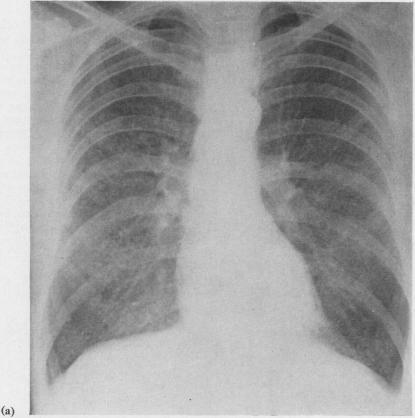

Allergic alveolitis in a maltworker.

A further example of diffuse pulmonary hypersensitivity to an inhaled organic antigen is reported. A 42-year-old maltworker, who developed an illness resembling farmer's lung, was found to have been heavily exposed to the spores of Precipitating and complement-fixing antibodies against an extract of were detected in his serum, a late (Arthus-type) reaction was produced by intradermal injection of the same extract, and a pyrexial reaction, accompanied by a reduction in forced vital capacity and carbon monoxide transfer factor, occurred 6 hours after the inhalation of spores of Two of the patient's four workmates complained of similar but less severe symptoms, and their sera also contained specific antibodies. Although the spores of and of , the fungus responsible for maple-bark disease, are much larger than the 1 μ spores of sp., they may give rise to a diffuse pulmonary hypersensitivity reaction indistinguishable from that observed in farmer's lung. This suggests that the occurrence of such a reaction is not necessarily related to the size of the inhaled particles, and there is reason to believe that the concentration of spores or other antigenic particles in the inspired air may in this respect be more important than their size. The pulmonary hypersensitivity in this group of disorders appears to be a precipitin-mediated (type III) response to a variety of inhaled antigens, but some of these antigens may in certain patients, presumably atopic individuals, also provoke a reagin-mediated (type I) bronchial hypersensitivity reaction. It is suggested that a term such as allergic alveolitis' or extrinsic allergic alveolitis' may suitably be used to describe the group of diseases caused by pulmonary hypersensitivity to inhaled organic antigens.